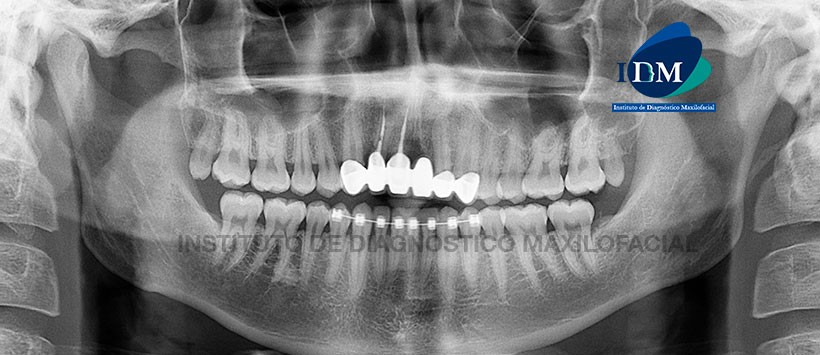

Paciente masculino de 22 años de edad, es referido al Instituto de Diagnóstico Maxilofacial – IDM para evaluación tomográfica pieza 2.1 por presentar dolor y movilidad.

En la radiografía panorámica (Figura 1), se aprecia piezas 1.2 y 1.1 coronas protésicas espigos y obturación de conducto. Pieza 1.1 aparente proceso de reabsorción radicular cervical.